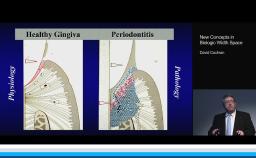

This presentation discusses the evolution of dental implant designs and the effects of various designs on peri-implant tissues. The biologic width around natural teeth is compared to the biologic width around implants. The main contemporary implant systems and types are discussed, and sound research is presented to explain the current understanding of dental implant components and macro designs. Butt joint, tissue level, and platform switching designs are compared, as well as external hex and internal conical implant-abutment connections. Biologic effects of different designs are presented, and clinical advice based on basic research is given at the conclusion.

- recognize the effect of dental implant designs and components on the surrounding tissues

- explain the soft and hard tissue response to different implant designs